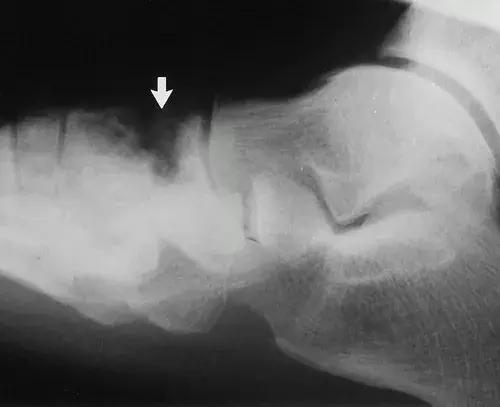

图17:42岁男性糖尿病人,踝关节和后足的神经性骨关节病。侧位X线片显示胫骨远端破坏吸收,并且具有类似于手术截肢的尖锐边缘。 距骨圆顶被吸收。 存在硬化,并且不再能够识别距下关节(箭头)。